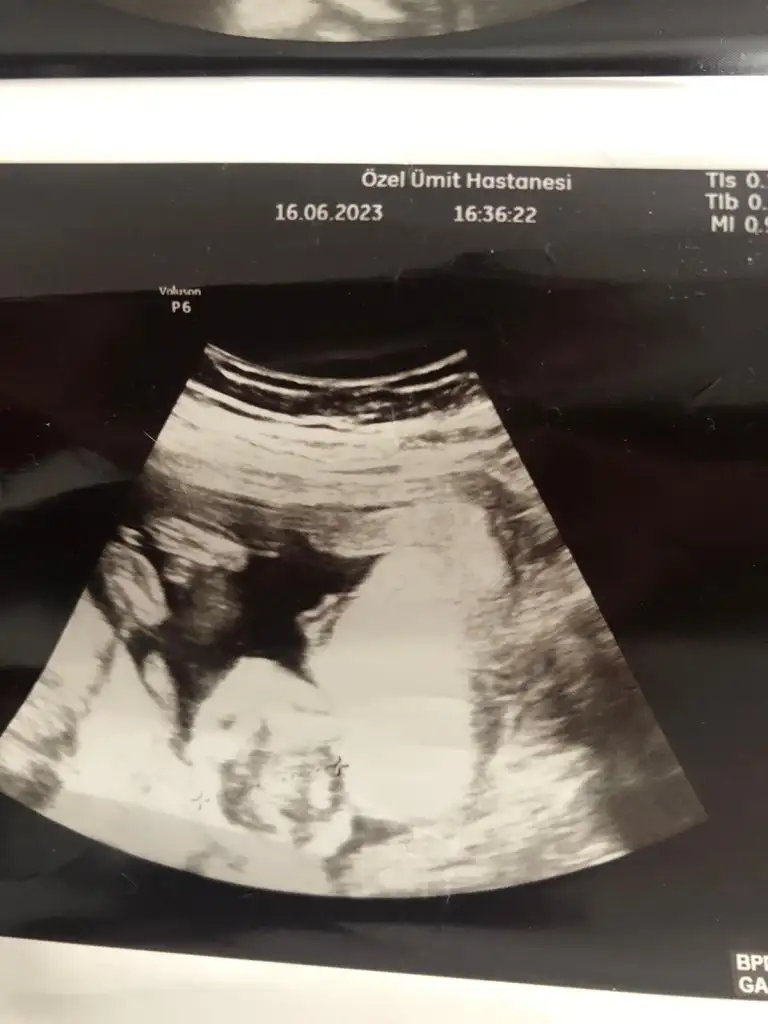

7+3 ve 6 haftalık görüntü tahmin yapar mısınız?

Eklentiler

• IMG_9439.webp

23,8 KB · Görüntüleme: 89

• IMG_9406.webp

32,3 KB · Görüntüleme: 99